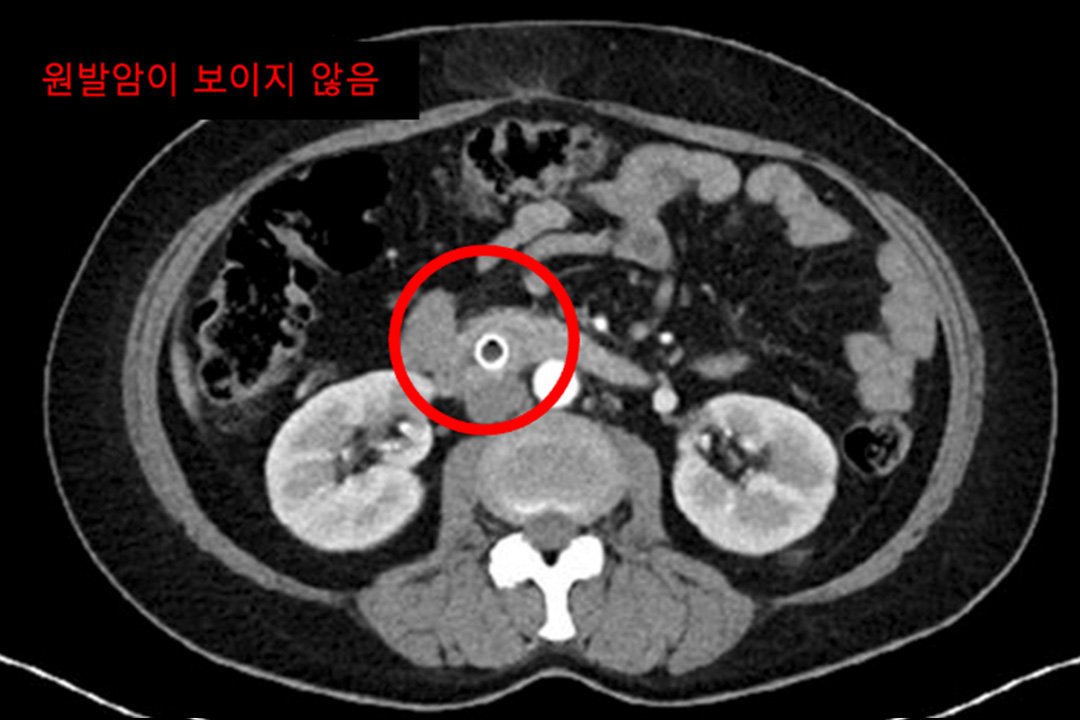

Case of treatment

아미랑에서 치료하신 분들의 소중한 치료사례를 담았습니다.